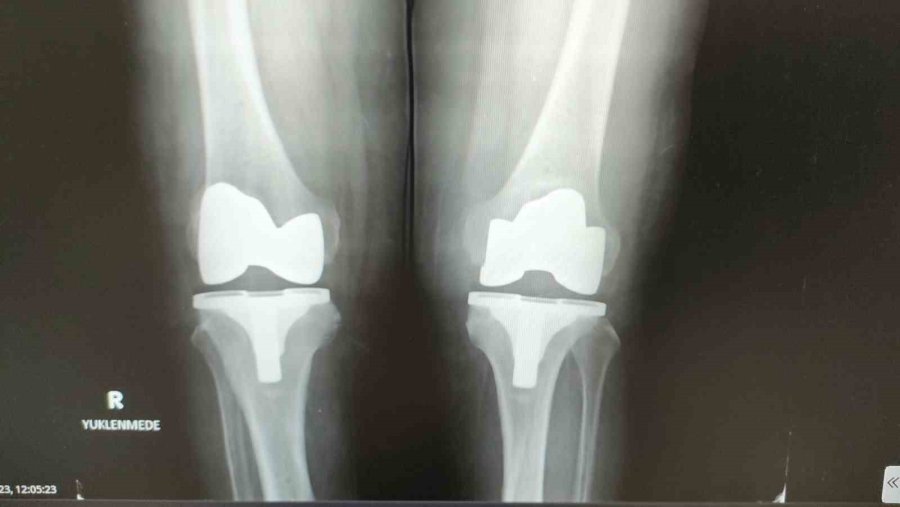

Protezin ağrılı bir işlemden önce uygulandığını dile getiren Baloğlu, "Kireçlenme dediğimiz durum olunca, iki kemik birbirine sürtüyor, hasta ayağa kalktığında, hatta sonraki dönemlerde istirahatte bile ağrıdan dolayı duramıyor. Bırakın yürümeyi normal istirahat ağrısı, gece ağrısı oluyor. Dolayısıyla bu hastalar bize, "Beni ameliyat edin" diye geliyor. Çoğu hasta grubumuz böyle. Robotik protezler diğer protezlere göre şöyle bir farklılığı var; biz bu protezi hastaya özel ürettiriyoruz. Ameliyat öncesinde tomografi ve filmler sisteme yükleniyor. Sistem sayesinde protezler hastaya özel üretildiği için, kişiye özel olarak gelmiş oluyor. Bu protezi robotik yardımlı olarak ameliyatta hastaya uyguluyoruz. Bu işlem kabaca yarım saat 45 dakika sürüyor" dedi.

Hastanın bir iki gün hastanede kaldıktan sonra yürür şekilde taburcu olduğunun altını çizen Baloğlu, "Bu ameliyatta daha az kesiden işlem yapıldığı hem de hastaya özel protez kullanıldığı için hata payımız neredeyse sıfır. Bu nedenle hasta da bir ay sonra geçirdiği bu işlemi neredeyse unutmuş olur.

Yürüme sıkıntısı çeken hasta rahatlıkla yürüyerek çıkıyor. Çünkü ağrı olmadığı zaman hasta zaten yürümek istiyor ve bunu biz de talep ediyoruz. Dolayısıyla bundan sonrasında, "aman yürüme üzerine basma" demiyoruz. Tam yükle mobilize olur şekilde hasta gidebilir buradan. Özellikle namaz kılma noktasında zorlanan yaşlılarımızdan çok soru geliyor. Robotik protezlerin dizaynında mobil dediğimiz hareketli protezlerde namaz kılma anlamında bir engel durum yok. Biz bunu gerekli rehabilitasyon yapıldıktan sonra hasta sandalye ya da başka bir şey kullanmadan namazını kılabilir" ifadelerine yer verdi.